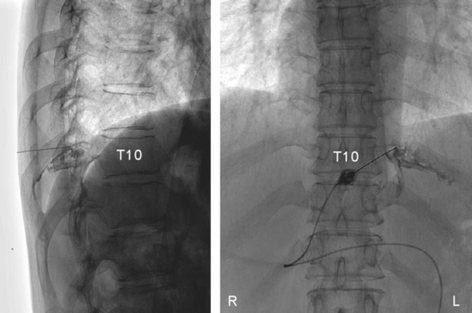

The patient was treated with an intercostal nerve block at T10 (Fig. 3) with 50 mg of mepivacaine hydrochloride (Carbocain, AstraZeneca, Inc., Japan) and 4 mg of dexamethasone sodium phosphate (DEXART, FujiPharma, Inc., Japan), and the pain subsided. Nine months later, the neuralgia recurred and another nerve block again relieved the pain. There was no recurrence 22 months after the last nerve block.